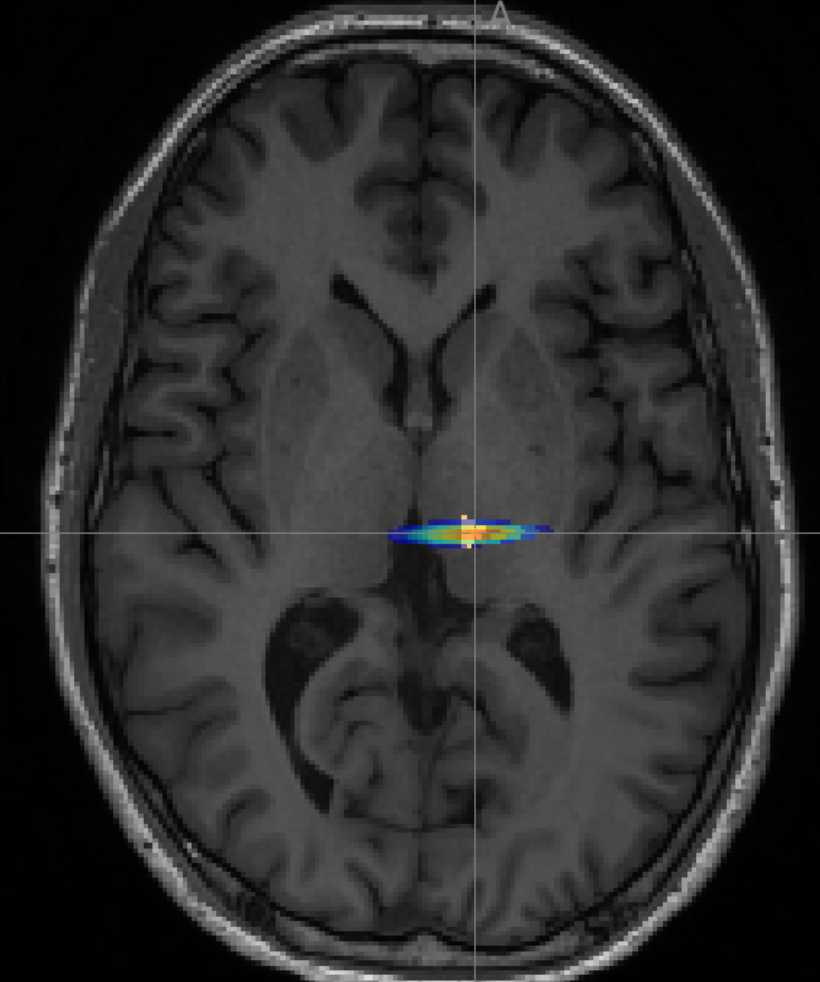

Transcranial ultrasound neuromodulation

Noninvasively modulating brain circuits with high spatial precision to enhance the way medications influence the brain (study ongoing, ask me for details).